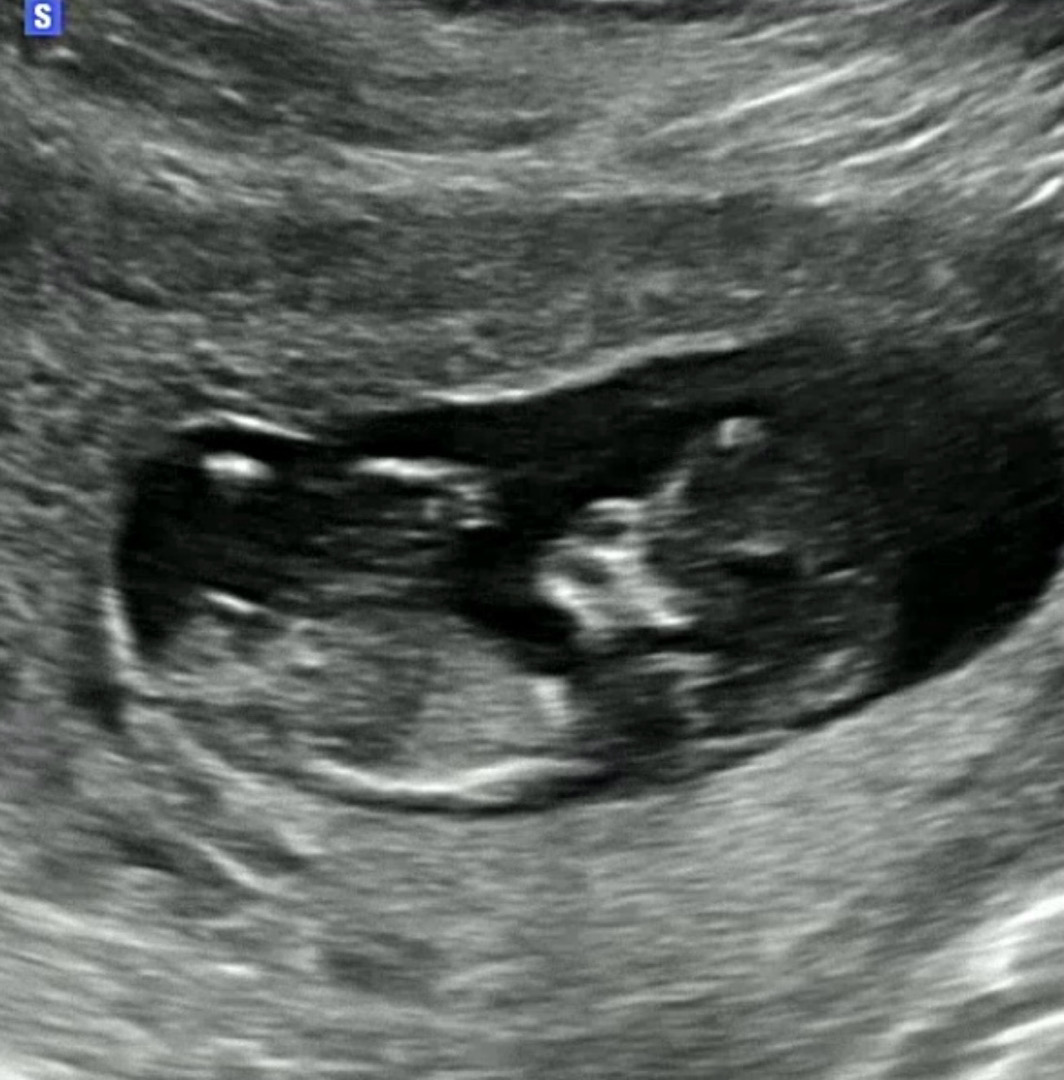

12주 초음파인데 각도법으로 봤을때 성별이 뭘까요??